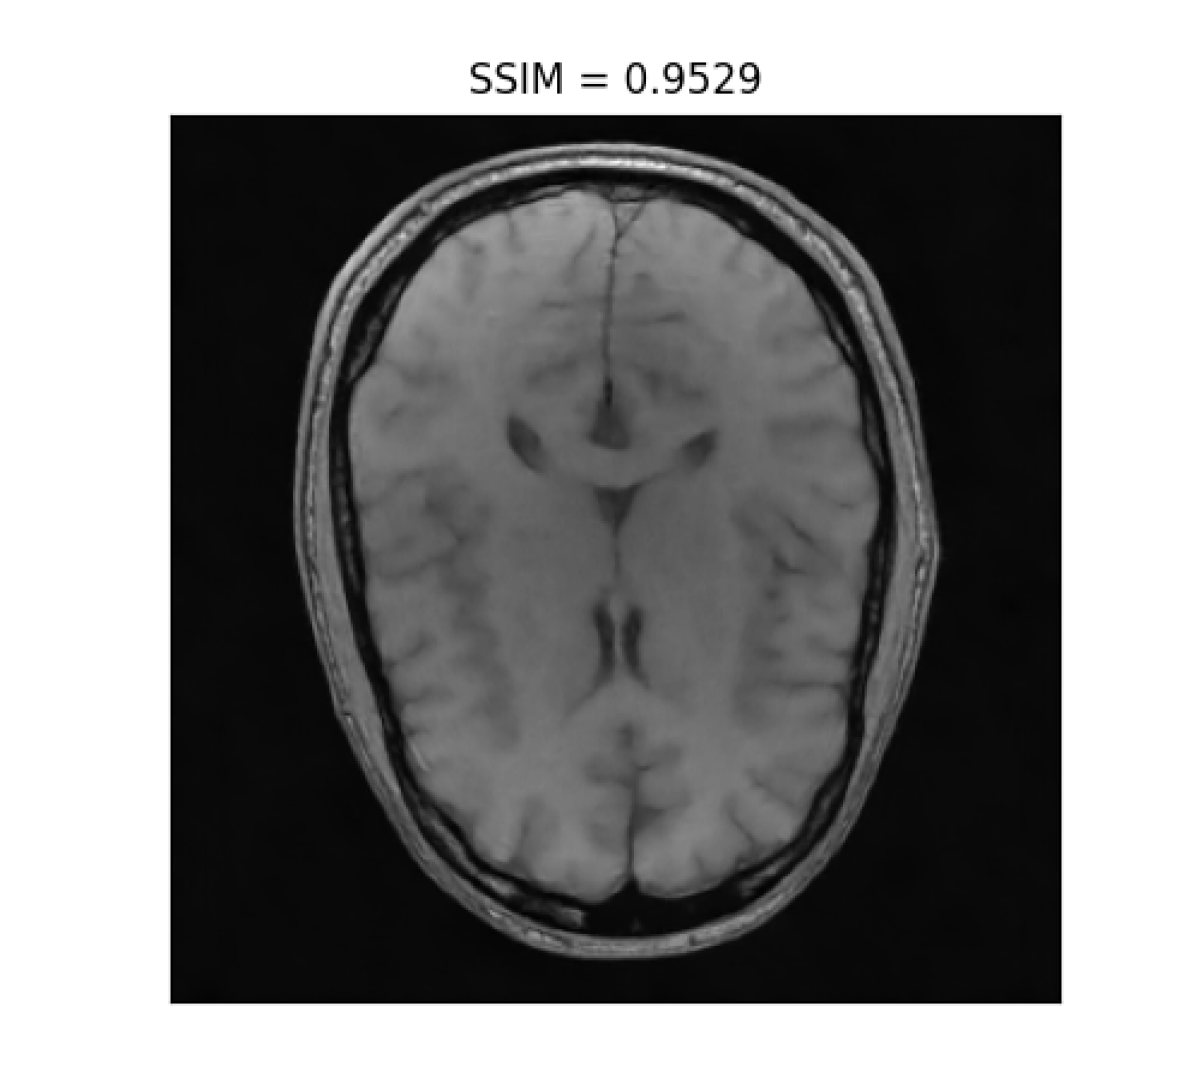

III-B2 Qualitative results

For visual inspection, we present the results of image reconstruction from data undersampled using SPARKLING trajectories generated for various target densities in Fig. 3 (T1subscriptT1\text{T}_{1}-w images) and Fig. 4 (T2subscriptT2\text{T}_{2}-w images). For the sake of space, we only report the best reconstruction results, i.e. with NC-PDNet. For T1subscriptT1\text{T}_{1}-weighted contrast, we show that all methods give similarly performing results, however 𝝆vdssubscript𝝆𝑣𝑑𝑠\boldsymbol{\rm\rho}_{vds} and 𝝆lbsubscript𝝆𝑙𝑏\boldsymbol{\rm\rho}_{lb} provide the best SSIM scores. Further, we observe that in this case, 𝝆vdssubscript𝝆𝑣𝑑𝑠\boldsymbol{\rm\rho}_{vds} is slightly better than 𝝆lbsubscript𝝆𝑙𝑏\boldsymbol{\rm\rho}_{lb}. On the contrary, for T2subscriptT2\text{T}_{2}-w contrast, 𝝆lbsubscript𝝆𝑙𝑏\boldsymbol{\rm\rho}_{lb} outperforms the other densities as reflected both visually in Fig. 4 and quantitatively (see Fig. 2).

Reference T1subscript𝑇1T_{1}-w Image (i) 𝝆vdssubscript𝝆𝑣𝑑𝑠\boldsymbol{\rm\rho}_{vds} (ii) 𝝆sbsubscript𝝆𝑠𝑏\boldsymbol{\rm\rho}_{sb} (iii) 𝝆lsbsubscript𝝆𝑙𝑠𝑏\boldsymbol{\rm\rho}_{lsb} (iii) 𝝆lbsubscript𝝆𝑙𝑏\boldsymbol{\rm\rho}_{lb}

Refer to caption Refer to caption Refer to caption Refer to caption Refer to caption

Figure 3: NC-PDNet-based image reconstruction for retrospective T1𝑇1T1-w imaging with slice 666 in file_brain_AXT1_201_6002725.h5 from validation data in fastMRI dataset for different target sampling densities.